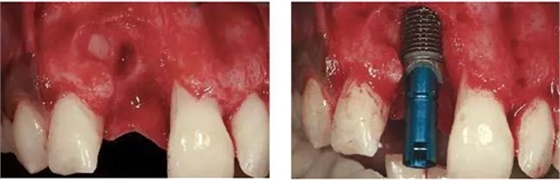

圖3、拔牙后看到更大范圍的骨缺損,并且缺損導(dǎo)致上頜側(cè)切牙根尖牙骨質(zhì)暴露,繼而存在術(shù)后由于軟硬組織退縮而帶來的美學(xué)風(fēng)險。

圖4、植入的種植體,初始穩(wěn)定性很好,由于骨缺損范圍大,選擇潛入式愈合。

圖5、種植體完全位于拔牙窩骨壁包圍的范圍內(nèi),距離唇側(cè)骨板至少2mm。